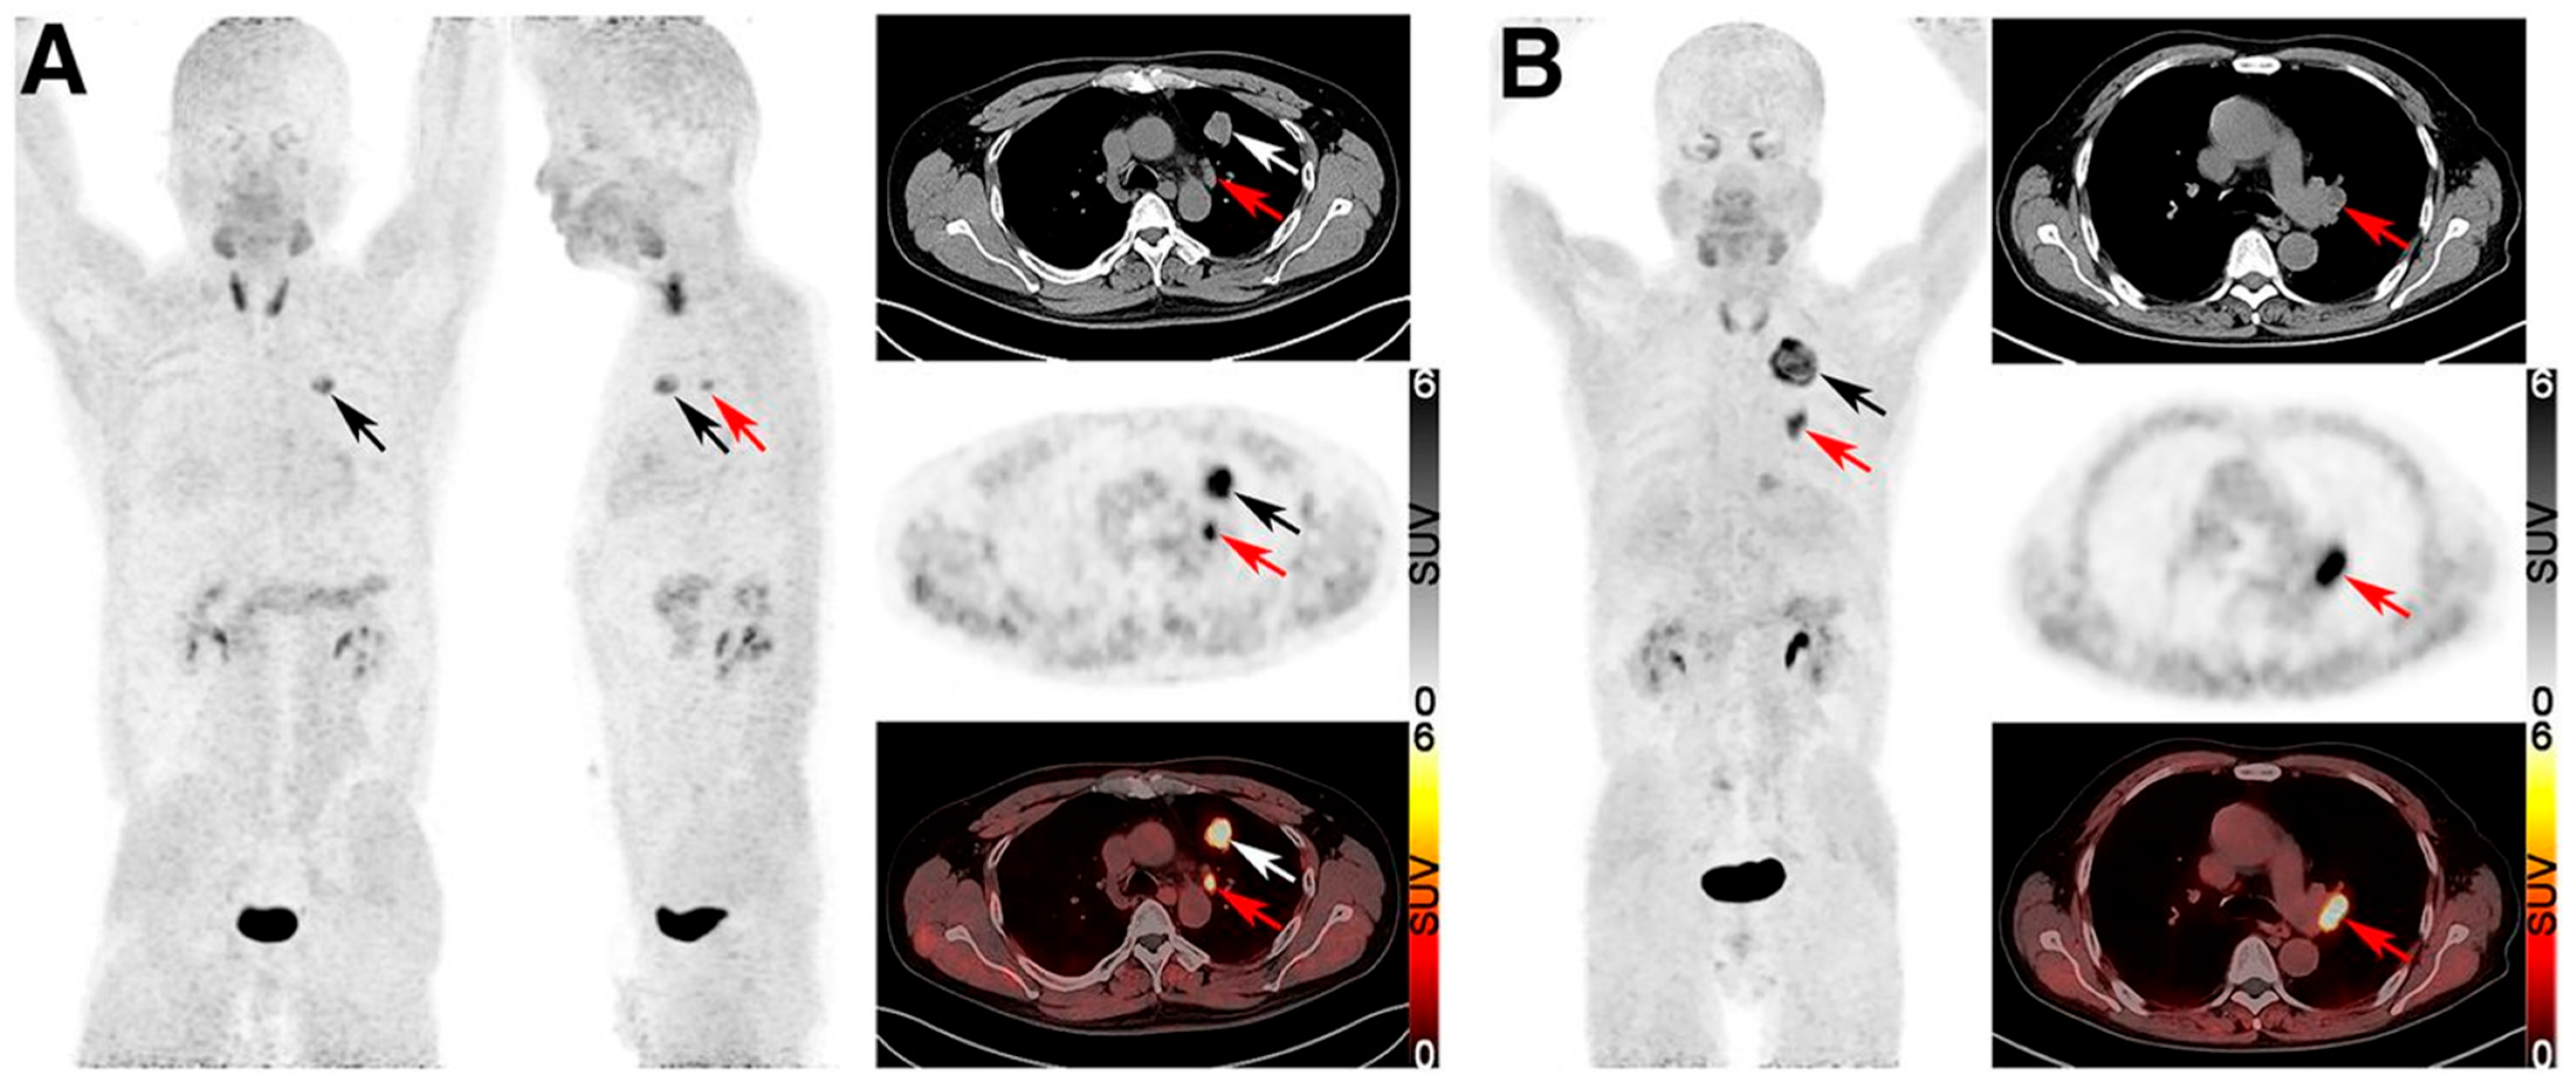

- FAP PET demonstrates superior sensitivity to FDG PET in detecting nodal and distant metastases, particularly in NSCLC.

- FAP PET outperforms FDG PET in identifying non-solid nodular lung ADC.